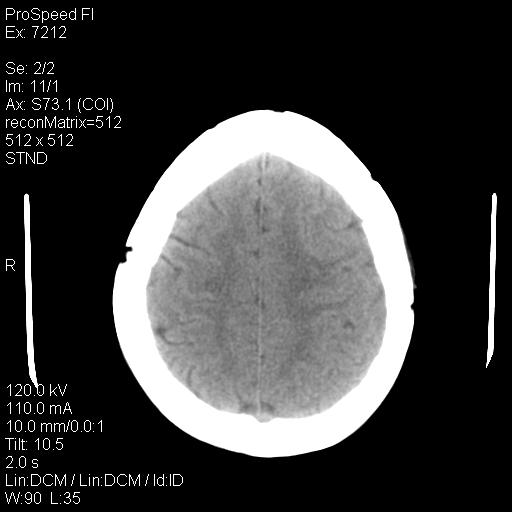

标题: CT18636:F 44Y,头痛三个月,左侧肢体麻木一周。临床诊断, [打印本页]

标题: CT18636:F 44Y,头痛三个月,左侧肢体麻木一周。临床诊断,

右额叶脑沟变浅,脑表面见新月形稍高密度影,考虑慢性硬膜下出血可能。

额顶骨多发穿凿样骨缺损区,不排除骨髓瘤等改变,进一步检查。

1)考虑左侧额部慢性硬膜下血肿(或硬膜下积液)。2)颅骨骨髓瘤不排除;建议行进一步检查。

1)考虑左侧额颞部及右侧额部慢性硬膜下血肿(或硬膜下积液)。2)颅骨骨髓瘤不排除;建议行进一步检查。

1)右侧半卵圆中心腔隙性脑梗塞。2)考虑左侧额部慢性硬膜下血肿(或硬膜下积液)。3)颅骨骨髓瘤不排除;建议行进一步检查。